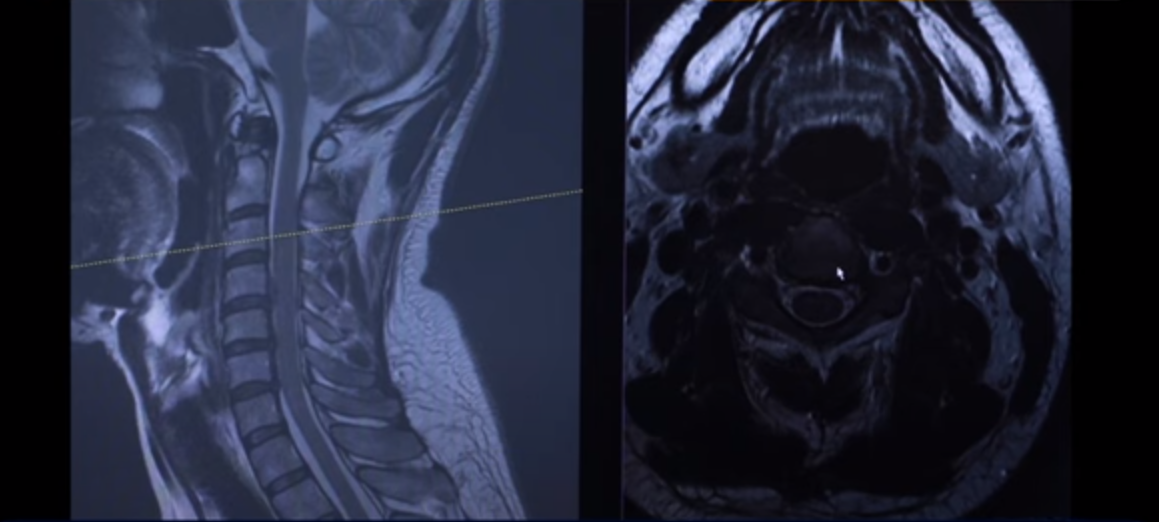

41세 목디스크 환자분 MRI 보도록 하겠습니다. 이분은 한 5년 동안 계속 목에 담결림 증상을 호소하시던 분입니다.

여기 MRI를 보시면 이렇게 세 마디에 퇴행성 목디스크가 있습니다. 보시다시피 희미하게 밀려서 올라간 게 보이실 겁니다. 디스크가 밀려서 올라간 겁니다.

그 다음 마디를 보시면 여기도 이렇게 좀 튀어나와 있습니다.

마지막 이 마디를 보시면 디스크가 조금 밀려서 올라가 있습니다. 이게 왼쪽으로 밀려 나와 있습니다.

이 환자분 증상이 목에 담결림 증상 외에도 왼쪽 어깨 쪽 증상과 왼쪽 손의 저림 증상입니다. 그래서 이것 때문에 왼쪽에 증상이 있다 이렇게 보시면 됩니다.